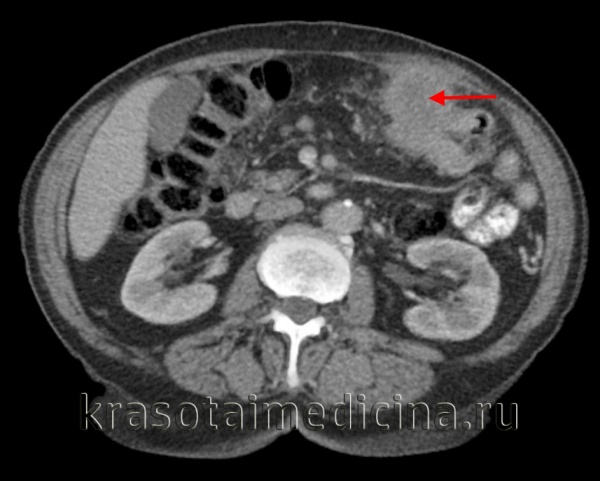

КТ ОБП. Опухоль поперечной ободочной кишки, прорастающая в переднюю брюшную стенку. (фото Вишняков В.Н.)